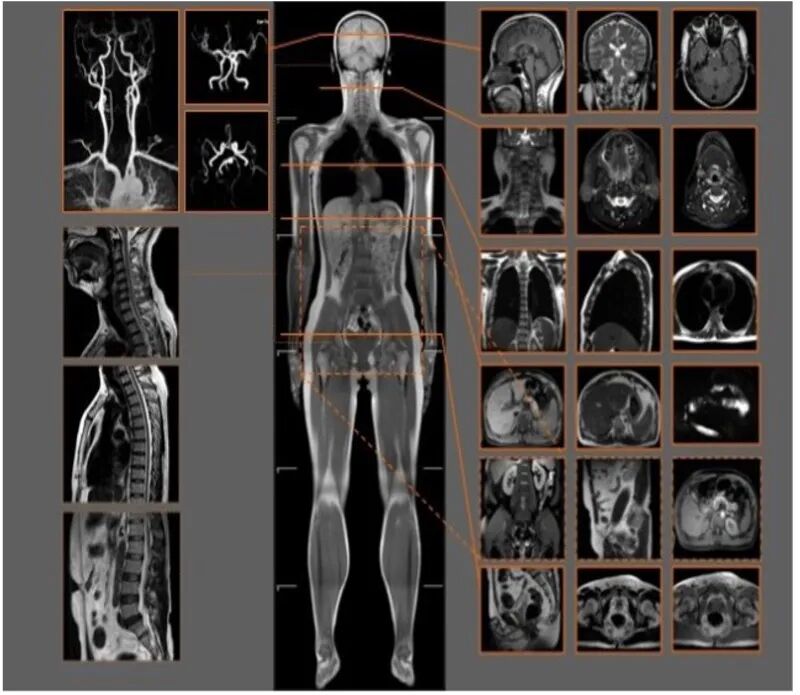

三、MRI也就是磁共振成像,属于断层成像的一种,它是利用磁共振现象从人体中获得电磁信号,并重建出人体信息。通过检查可获得横断面、矢状面、冠状面的影像,空间分辨率高,是神经系统、脊柱脊椎部分检测的第一选择,核磁共振仪器启动后可以对人体施加特定频率的射频脉冲,使人体中的氢质子受到激励,从而发生磁共振现象,产生某种能够生成图像的信号。无论是DR还是CT,由于对部分软组织的分辨率不足,所以软组织疾病的排查便成了它们的短板,而磁共振的长处恰恰就是清晰显示软组织疾病,对于膀胱、直肠、子宫及关节肌肉的检查优于CT。

X光拍片为什么要等都是拍片,DR、CT、MRI,到底啥区别?_https://www.jmylbn.com_新闻资讯_第12张

MRI检查适用于神经系统病变、心血管系统、胸部病变、全身软组织病变等。MRI的优点就是对人体不会产生电离辐射的伤害,可获得原生三维断面成像而无需重建就可以获得多方位的图像。但MRI的缺点和CT一样,很多病变单凭MRI仍然难以确诊,不像内窥镜可以同时获得影像和病理两方面的诊断,带有心脏起搏器、动脉瘤夹、人工金属心脏瓣膜、幽闭恐惧症患者、重症患者以及正在备孕期或已怀孕的女性都不能进行MRI检查。